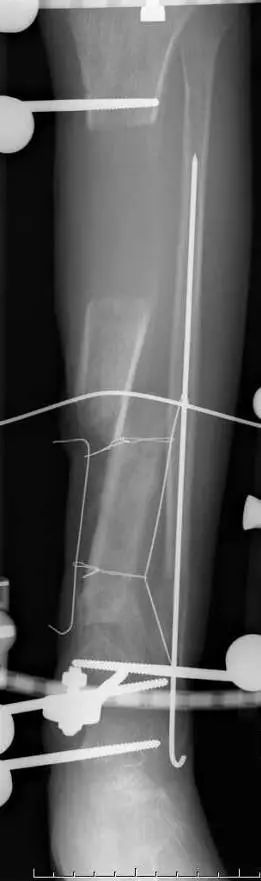

患者,男,56岁,脑外伤及下肢开放伤,急诊手术未使用双氧水,生理盐水冲洗伤口,外固定架固定,伤口游离植皮闭合。骨折及伤口获良好愈合

化繁为简固定法

选择进针点,避开重要结构。

Tips

• 按照多段骨折化繁为简固定方式复位固定近端骨折实现闭合处理。

• 创面新鲜后植游离皮

• 尽快下地走路,生理应力促进骨愈合

• 近端3个月愈合,远端用8个月

• 而后去除外固定架

• 如果使用双氧水会造成骨膜破坏,骨坏死外露,而后骨缺损,需要皮瓣植骨或骨搬运。